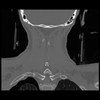

13 P.BLANDAS,,Coronal,2.000,P.BLANDAS,Coronal,